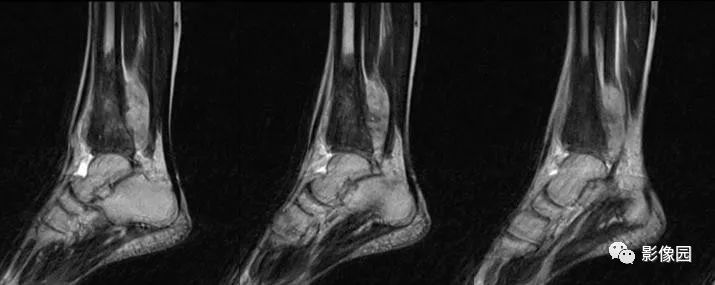

评论:前片X线示左胫骨下段及干骺端病变,髓腔内密度不均匀增高,内侧骨皮质可见骨质破坏,可见骨膜反应。CT示病灶内见多发斑片状肿瘤骨(黄色箭头),周围可见针状骨膜反应(红色箭头)。周围软组织肿胀。MRI示胫骨下段以长T1、长2信号为主的混杂信号影,未跨越胫距关节面,周围未见明显软组织肿块。周围软组织广泛片状长T1长T2信号影。复查X线示病变较前片明显进展,左侧胫骨远段及干骺端骨质破坏,周围可见针状骨膜反应及Codman三角(蓝色箭头)形成。相邻左侧腓骨下端、距骨滑车受累。